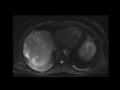

Large Hepatocellular Carcinoma (Hepatoma) (HCC)

MRI images demonstrate a large infiltrative mass in the liver with arterial hyperenhancement, delayed washout, and T2 hyperintensity, compatible with hepatocellular carcinoma (HCC).